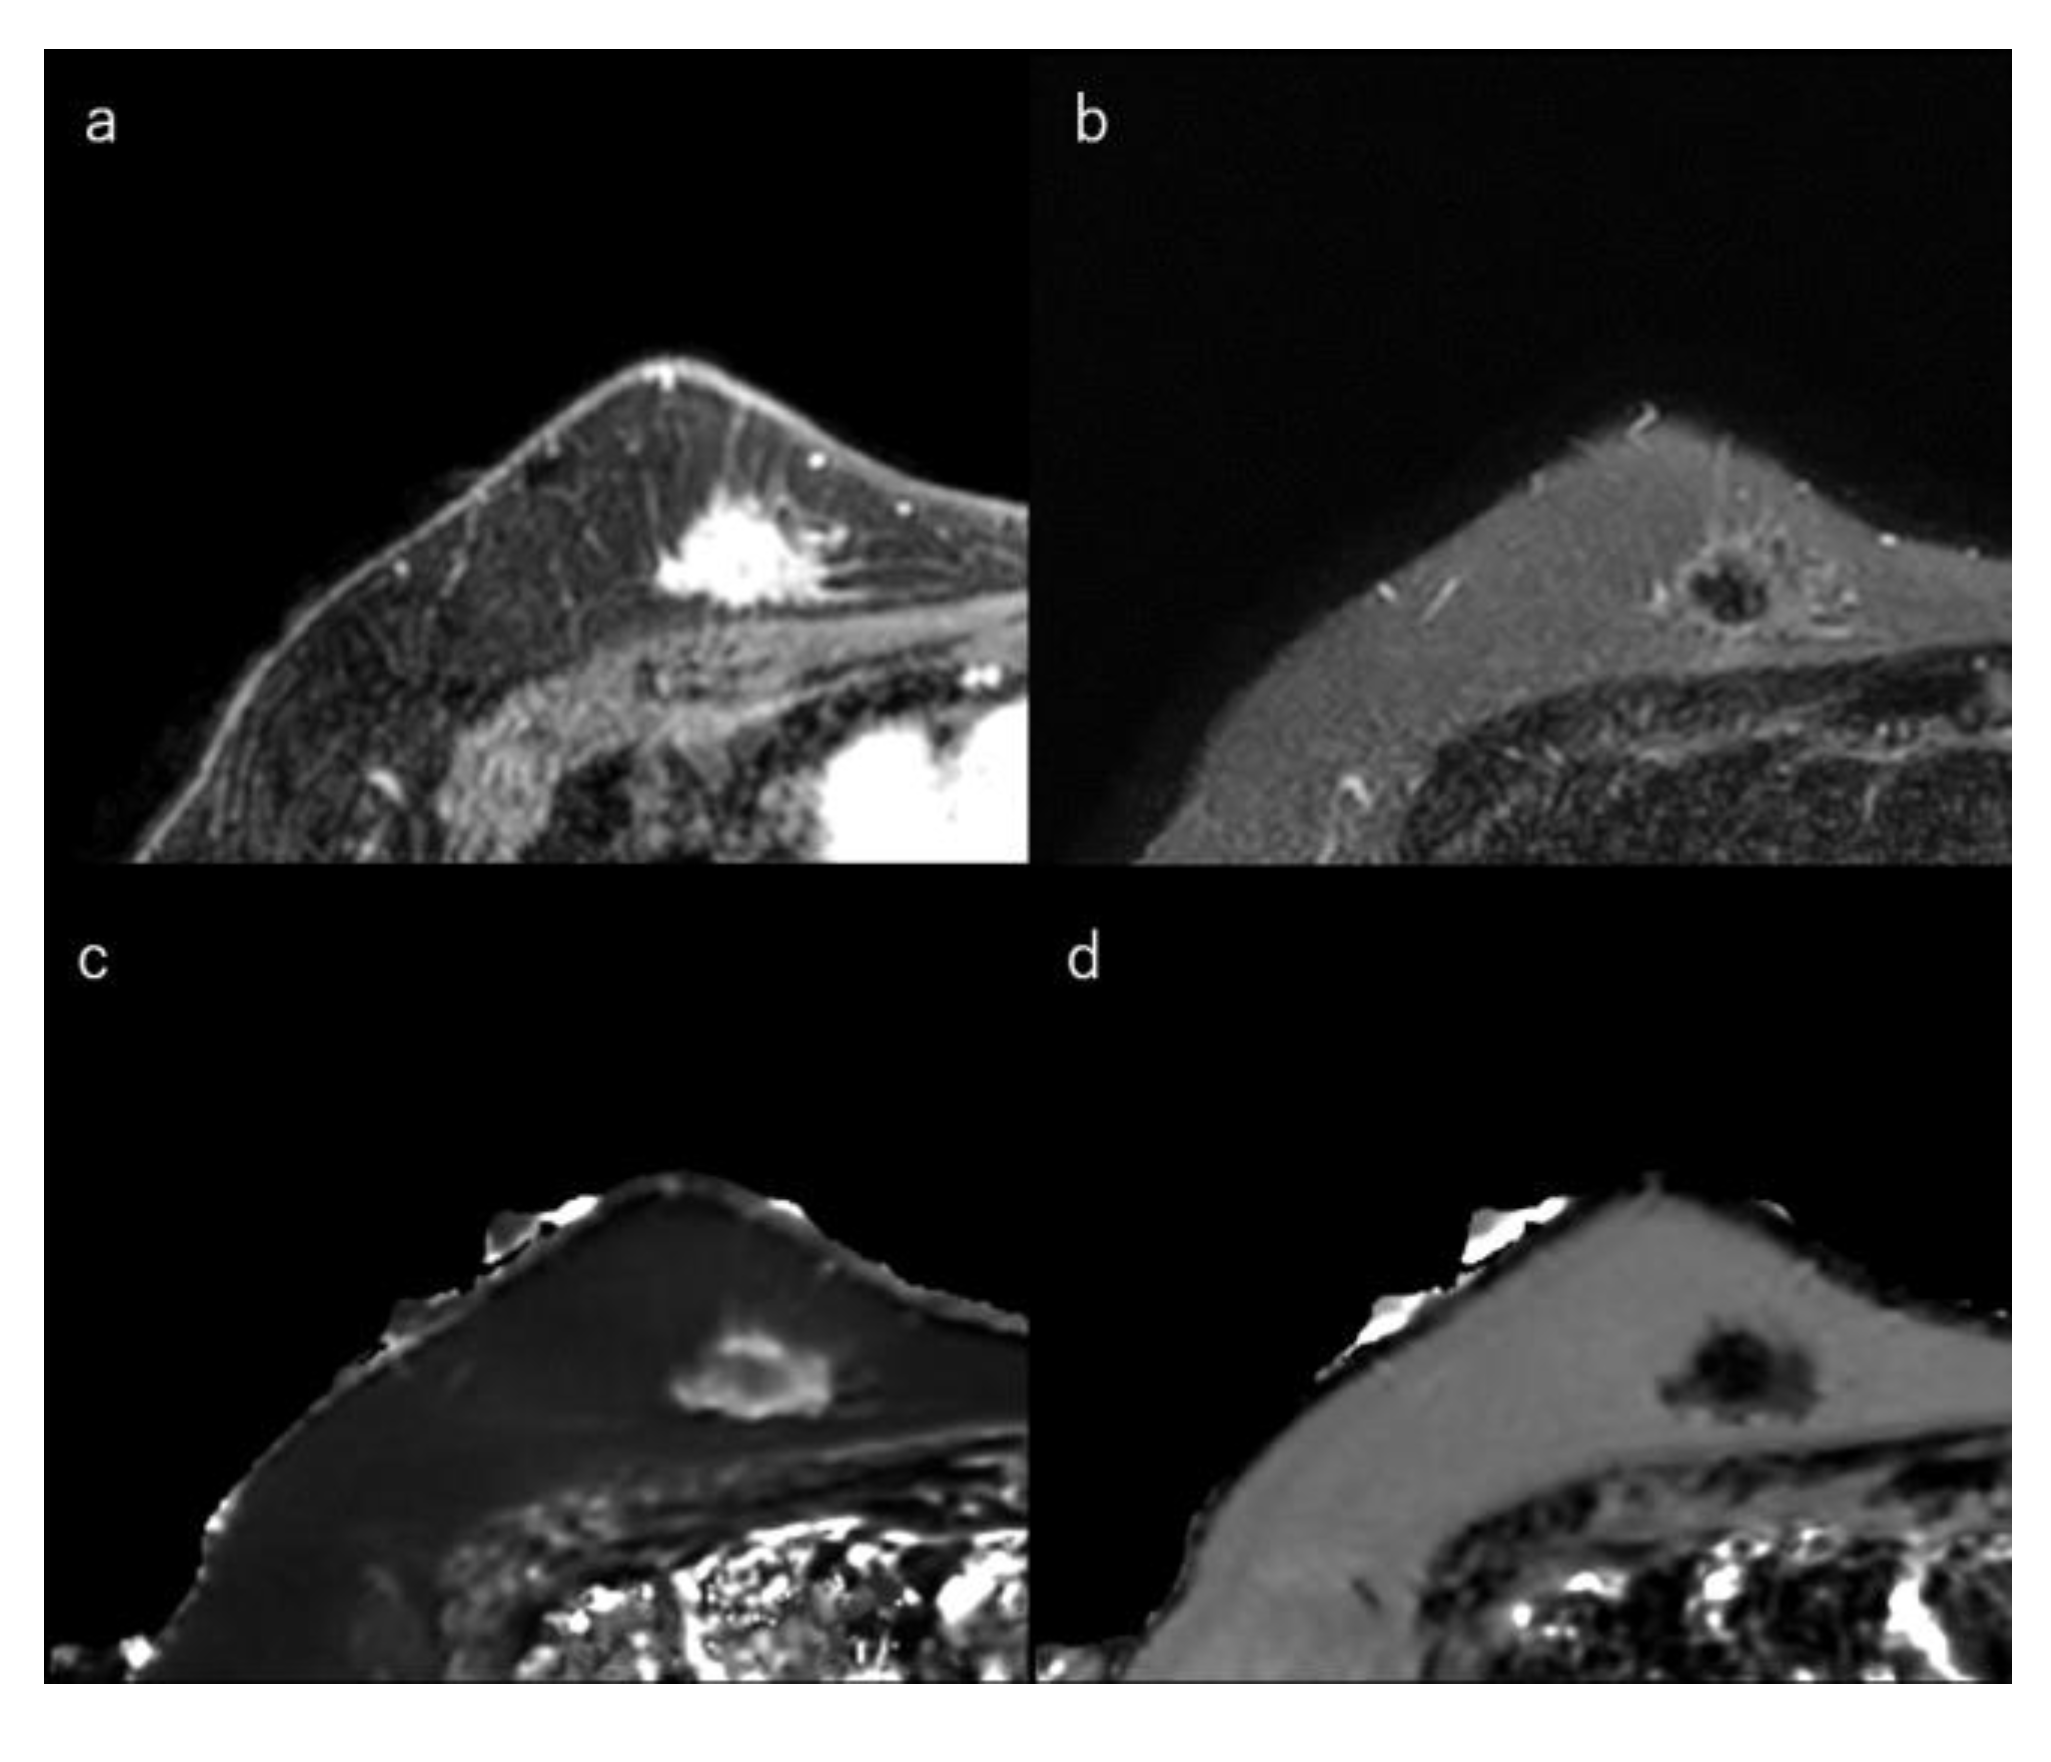

Figure 3.

(a) Dynamic contrast-enhanced MR image in a 50-year-old woman with luminal-A type breast cancer shows a spiculated mass. (b) Short-tau inversion recovery image shows a low signal mass. (c) T1 map (window width/centre = 1400/2400 ms) shows an intermediate signal mass; Mean T1 of the mass is 986 ms. (d) T2 map (window width/centre = 160/240 ms) shows a low signal mass; mean T2 of the mass is 62 ms.

This section explains the MRI characteristics of the breast cancer subtypes. In general, HR-positive tumours demonstrated stromal reaction, fibrosis, and perilesional spiculations [139]. An irregular mass margin and a non-round shape were significantly associated with luminal-A-type cancers [32,140,154]. Intratumoral iso/low T2-signal intensity may reflect fibrosis and is also associated with the luminal subtypes [14,140,141,142]. Multifocal or multicentric carcinoma is less common in the luminal-A type than in the luminal-B or HER2 types [140,155]. Compared to the other subtypes, luminal-A-type breast cancers tended to show less strong enhancement [35]. Kato et al. reported that rim enhancement occurred significantly less frequently in luminal-A-type breast cancers [85] (Figure 3).

In general, HR-positive tumours, which often have low proliferation, may demonstrate stromal reactions and fibrosis [139]. Intratumoral iso/low T2-signal intensity is a feature of breast cancer, which may reflect this fibrosis (Figure 3) [14,140,141,142,143]. In contrast, TN breast cancers have high signal intensity on T2-weighted images owing to necrosis [29,144,145,146]. In addition, a higher tumour grade often correlates with higher neoangiogenesis [128]. Angiogenesis increases total extracellular fluid volume and oedema. Thus, high-grade tumours may demonstrate high signal intensity on T2-weighted images. High signal intensity on T2-weighted images is also correlated with tumour grade [106,147,148,149].